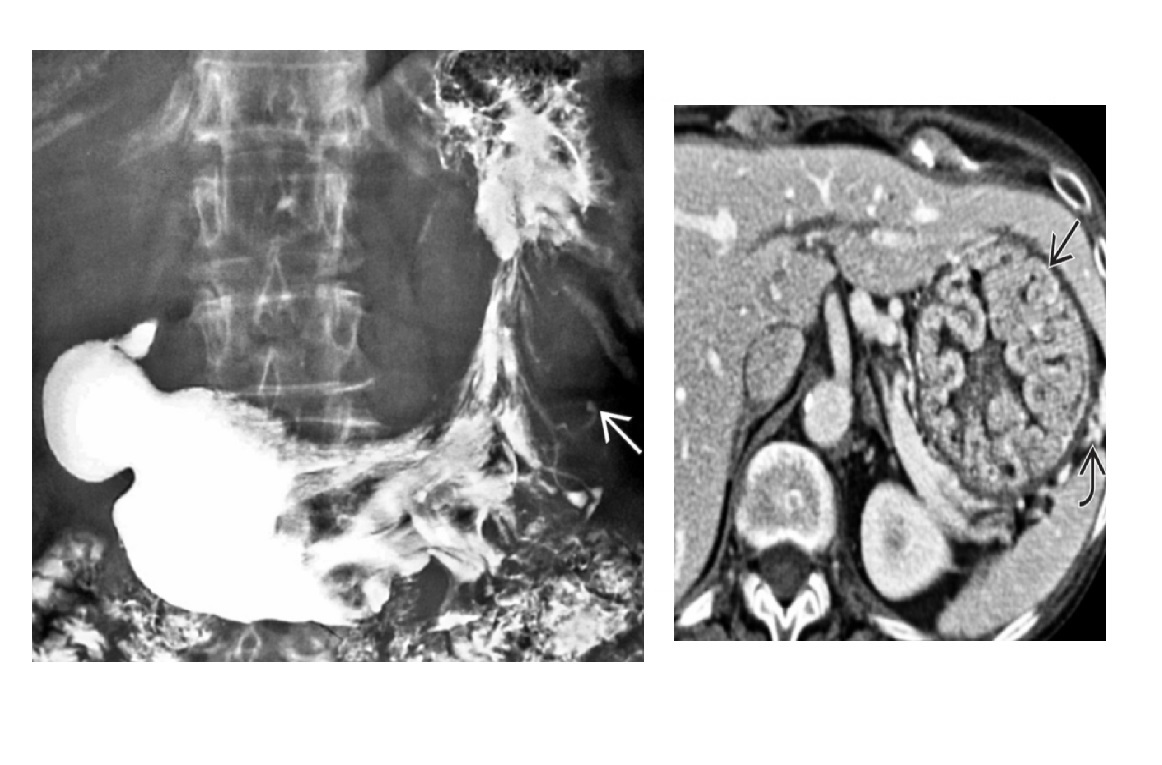

Pseudomyxoma peritonei Low-attenuation masses (usually < 20 HU) scattered throughout peritoneum Thick walls, septa and calcificaiton 'scalloped appearance'/displace of liver and spleen **Mucocele** Dominant cystic or solid mass often present in right lower quadrant/tip caecum (in expected location of appendix) . +/- curvillenar calcifcation Mucin-producing neoplasm of appendix causes appendiceal distention and subsequent perforation with diffuse intraperitoneal spread of mucinous implants DDx Peritoneal carcinomatous - discrete tumour Implants are solid -Rarely may cause "scalloping" TB peritonitis - Ascites and omental/mesenteric fat stranding with symmetric, smooth enhancement and thickening of peritoneal lining -can be loculated - look for including low-attenuation mesenteric nodes and thickening of cecum and terminal ileum